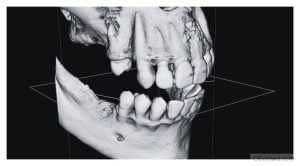

Learn how to maximize the diagnostic value of Cone Beam Computed Tomography (CBCT) while minimizing radiation exposure for safer imaging and smarter decision-making in dentistry.

MRI & CBCT | WHAT DENTISTS NEED TO KNOW

Implant Radiology | Myths vs. Facts